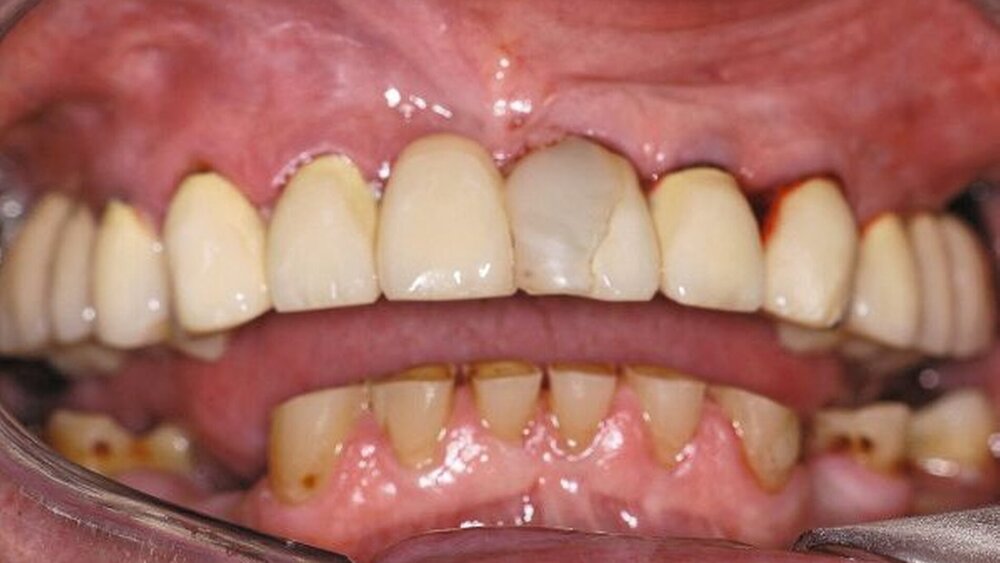

Im Rahmen der intraoralen Befunderhebung wurde festgestellt, dass die Gingiva insgesamt gerötet und ödematös war. Die Messung der Taschentiefe ergab einen durchschnittlichen Wert von fünf mm. Der ermittelte PSI (in Bezug auf die Sechstanten) ergab die Werte 4, 2, 4, 3, 2, 2. Pusaustritt konnte in regio 17 und in regio 27 festgestellt werden, so dass der Erhalt dieser Zähne fraglich war. Im Oberkiefer lag ein prothetisch versorgtes Lückengebiss der Kennedy-Klasse III2 vor. Die Zähne 18, 16, 15, 11, 25, 26 und 28 fehlten. Die prothetische Versorgung bestand aus einer Brücke 17 bis 14 zum Ersatz von 16 und 15, einer Brücke 13 bis 23 zum Ersatz von 11 und einer Brücke 24 bis 27 zum Ersatz von 25 und 26. Sämtliche Brückenanker wiesen Randundichtigkeiten und Sekundärkariesbildung auf. An 21 konnte eine großflächige Keramikabplatzung festgestellt werden. 17 und 27 reagierten im Perkussionstest stark positiv. Im Rahmen einer Sensibilitätsprüfung mittels CO2-Schnee reagierten die Zähne 17, 22 und 27 negativ. Im Unterkiefer lag ein Gebiss der Kennedy-Klasse II3 vor. Die Zähne 38, 36, 34, 44, 45, 47 und 48 fehlten. Die Zähne 37, 42, 46 waren mit Füllungen versorgt, die erhebliche Undichtigkeiten aufwiesen. 46 reagierte im Kältetest negativ. Alle Unterkieferzähne wiesen starke Attritionen auf. Diese Zähne 33 bis 43 sowie 37 und 35 reagierten im Kältetest stark schmerzhaft (Abbildungen 4, 5).